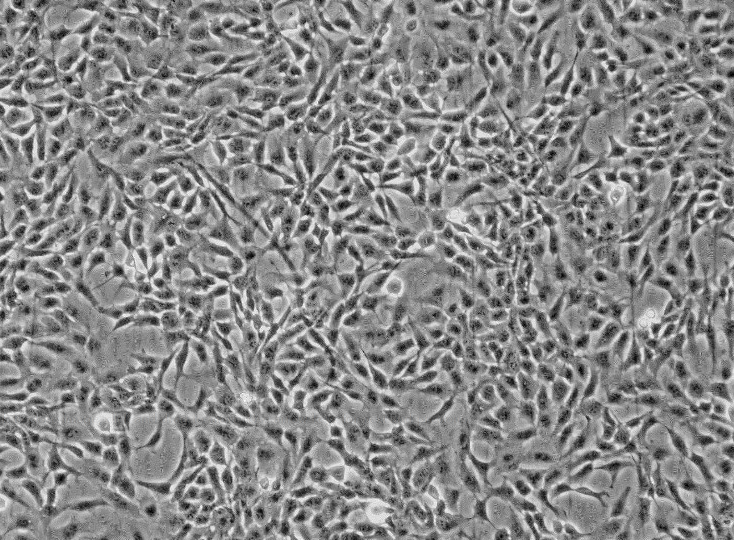

- 细胞形态:

淋巴母细胞样

形态:淋巴母细胞

背景资料:该细胞可产生5-羟色胺、ACTH和甲状旁腺素。角蛋白、波形蛋白弱阳性。